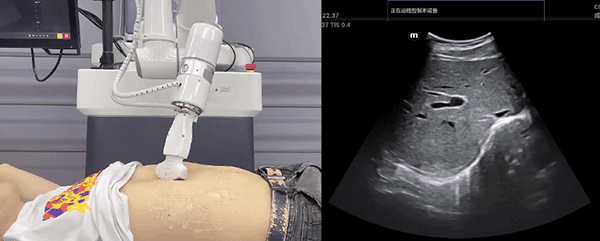

艾利特机器人末端搭载超声探头,可以对浅表小器官和外周血管、腹部(肝、胆、胰、肾等器官)进行超声检查。

目前,艾利特机器人在生物医药、医疗健康领域的赋能已有显著进展,艾利特协作机器人应用场景覆盖了临床试验、试管检测、拭子采集、试管搬运、荧光检测、康复治疗、超声扫查、导诊、消毒、微创治疗、针灸刮痧等。